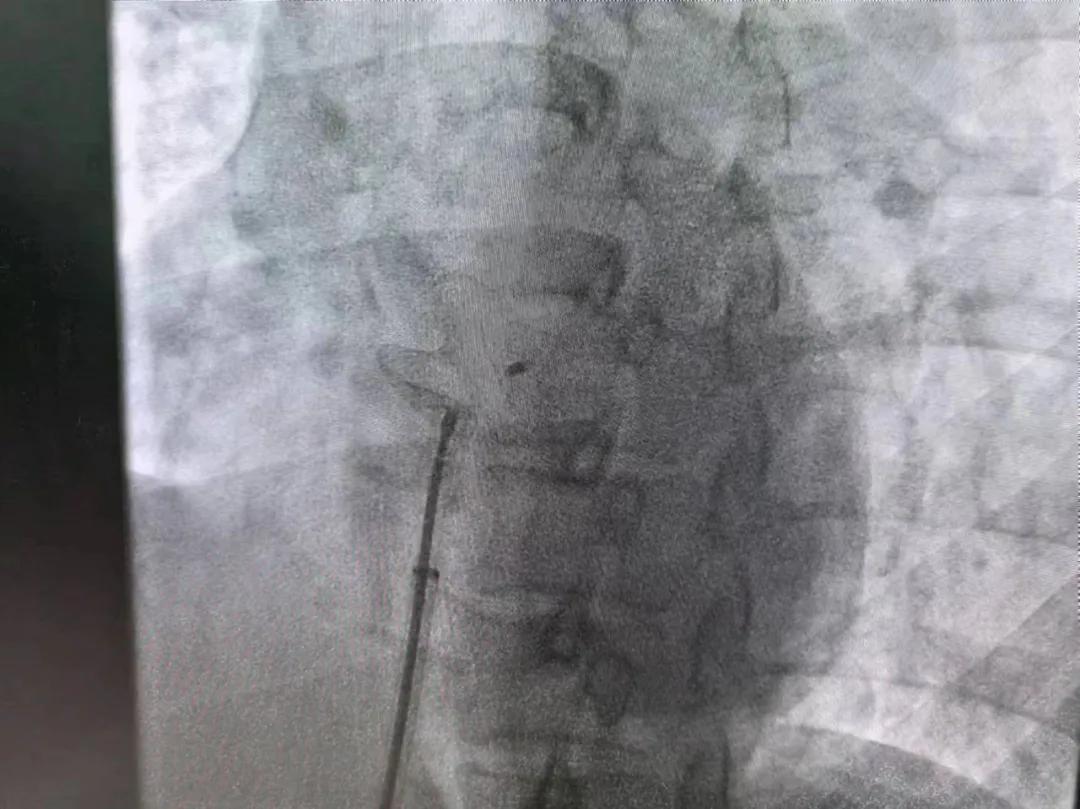

市二院:先天性心臟病介入診療 再創佳績

繼3月14日市二院成功開展首例卵圓孔未閉介入封堵術之后,3月21日上午,市二院院長王瑾及心血管內科主任李慧新帶領心血管內科介入團隊,再次成功為患者實施“經皮房間隔缺損封堵術”,手術過程順利。該例病人的成功手術及康復,標志著市二院心血管內科在結構性心臟病介入診療中再次達到了新高度。

患者為中年女性,41歲,近2年一直反復出現頭暈、頭痛,曾先后在多家醫院就診。近期患者癥狀加重,出現活動后氣喘合并胸悶癥狀,來到心血管內科就診。經心臟彩超檢查顯示:患者房間隔下段連續性中斷,缺損直徑達到了13mm,肺動脈壓已經輕度增高,確診為房間隔缺損。

于是,院長王瑾會診后,詳細詢問患者病史,認真分析臨床癥候群并準確診斷,耐心做好患者及家屬病情告知和充分溝通。經過完善的術前評估及準備,心血管內科介入團隊成功為患者實施“經皮房間隔缺損封堵術”,手術過程順利。近日,患者已順利康復出院。 (尹紅婭 潘長林)